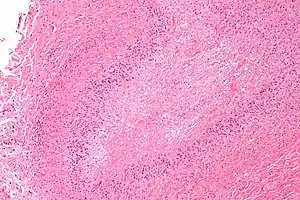

| Micrograph of a rheumatoid nodule, showing the characteristic palisading granuloma with a core consisting of necrotic collagen and fibrin. H&E stain. | |

Histological examination of nodules shows that they consist of a shell of fibrous tissue surrounding a center of fibrinoid necrosis.[11] Pea-sized nodules have one centre. Larger nodules tend to be multilocular, with many separate shells or with connections between the necrotic centers. Individual necrotic centers may contain a cleft or several centers of necrosis may all open on to a large bursal pocket containing synovial fluid.

The boundary between the necrotic center and the outer fibrous shell is made up of the characteristic feature of the nodule, which is known as a cellular palisade. The palisade is a densely packed layer of macrophages and fibroblasts which tend to be arranged radially, like the seeds of a kiwifruit or fig.[11] Further out into the fibrous shell there is a zone that contains T cells and plasma cells in association with blood vessels.[12] The histology of pulmonary nodules are similar to that of subcutaneous nodules, with central necrosis surrounded by palisading macrophages and inflammatory infiltrate.[5]